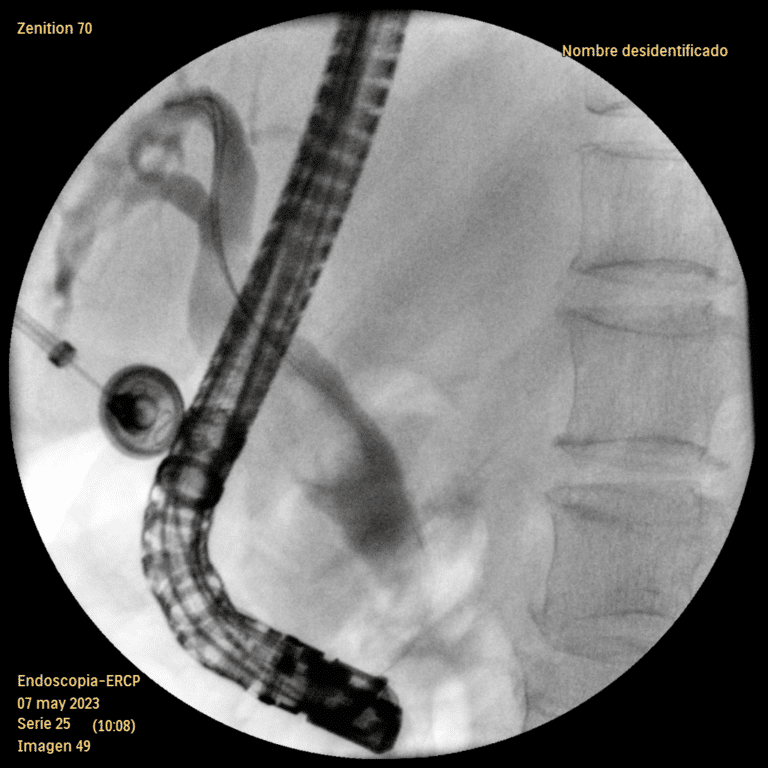

CPRE cerca de Querétaro – Manejo Especializado de Enfermedades Biliares y Pancreáticas La Colangiopancreatografía Retrógrada Endoscópica (CPRE) es un procedimiento terapéutico esencial para el manejo de patologías como la coledocolitiasis, pancreatitis biliar, estenosis de la vía biliar, ictericia obstructiva y…